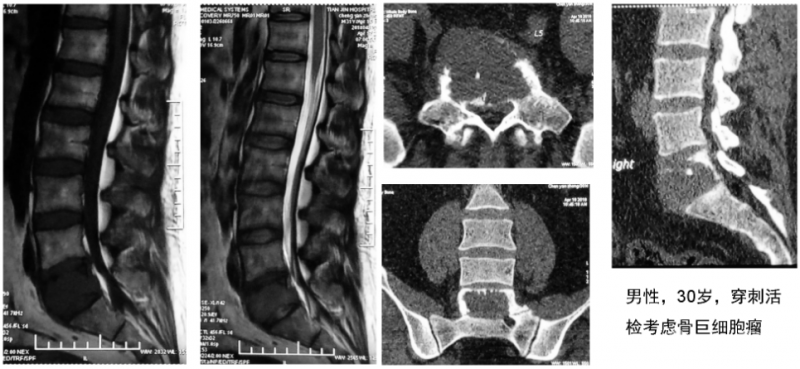

此前,有一例腰5椎体肿瘤患者在前路切除后进行椎体重建,以往临床上都是在术中给患者翻身进行后路固定。马信龙教授团队在做术前设计时,就给这名患者设计了个性化人工椎体,预留了假体与骨结合部位从前向后打椎弓根钉的孔,不需要患者翻身进行后路固定就获得了稳定性,临床效果令人满意。此例前路腰骶部病变切除后采用自主设计的3D打印假体重建椎体稳定性的病例,尚属国际首例。

一例前路腰骶部病变患者术前影像片